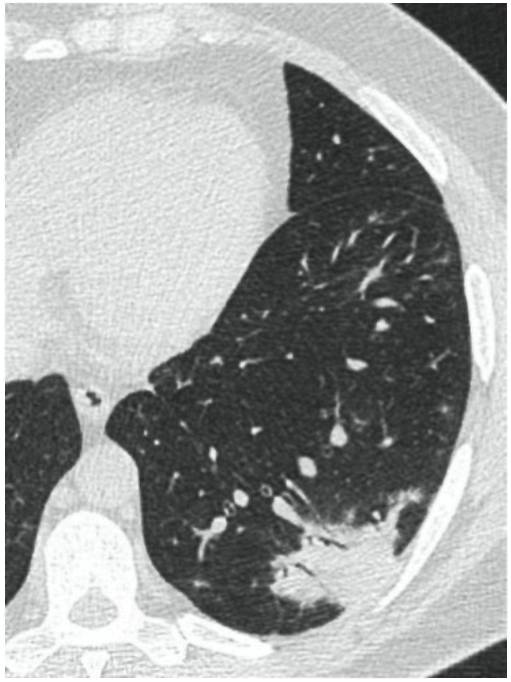

Консолидации кт

Консолидации кт 116 фотографий